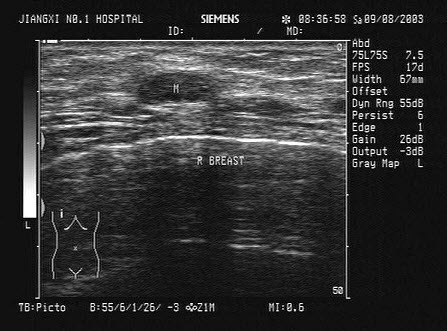

40、单项选择题

某患者自诉乳腺可触及一包块,光滑可移动,超声图像如图,诊断为()